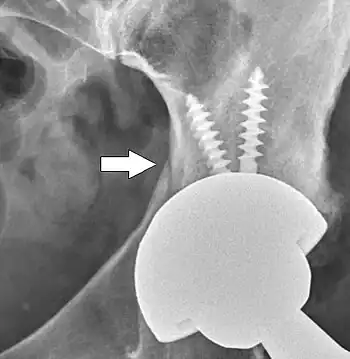

Metal on metal prosthetic hip

Cement-free implant sixteen days after surgery. Femoral component is cobalt chromium combined with titanium which induces bone growth into the implant. Ceramic head. Acetabular cup coated with bone growth-inducing material and held temporarily in place with a single screw.

The prosthetic implant used in hip replacement consists of three parts: the acetabular cup, the femoral component, and the articular interface. Options exist for different people and indications. The evidence for a number of newer devices is not very good, including: ceramic-on-ceramic bearings, modular femoral necks, and uncemented monoblock cups.[89]

Acetabular cup

The acetabular cup is the component which is placed into the acetabulum (hip socket). Cartilage and bone are removed from the acetabulum and the acetabular cup is attached using friction or cement. Some acetabular cups are one piece, while others are modular. One-piece (monobloc) shells are either ultra-high-molecular-weight polyethylene or metal, they have their articular surface machined on the inside surface of the cup and do not rely on a locking mechanism to hold a liner in place. A monobloc polyethylene cup is cemented in place while a metal cup is held in place by a metal coating on the outside of the cup. Modular cups consist of two pieces, a shell and liner. The shell is made of metal; the outside has a porous coating while the inside contains a locking mechanism designed to accept a liner. Two types of porous coating used to form a friction fit are sintered beads and a foam metal design to mimic the trabeculae of cancellous bone and initial stability is influenced by under-reaming and insertion force.[90] Permanent fixation is achieved as bone grows onto or into the porous coating. Screws can be used to lag the shell to the bone providing even more fixation. Polyethylene liners are placed into the shell and connected by a rim locking mechanism; ceramic and metal liners are attached with a Morse taper.